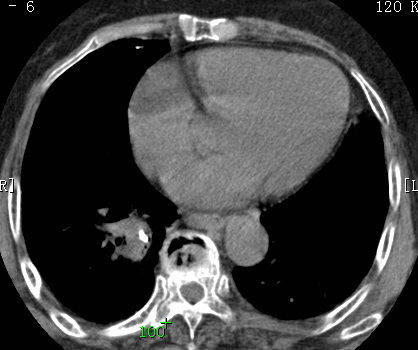

标题: CT26680:肺部右下肺静脉干结节的界定 [打印本页]

标题: CT26680:肺部右下肺静脉干结节的界定

增强适应症

考虑1、周围型肺癌,2肺静脉畸形,前者可能大,建议增强检查。

考虑1、周围型肺癌,2肺静脉畸形,前者可能大,建议增强检查。支持!

不排除右肺下叶周围型肺癌可能。

中心型肺癌,纤支镜可帮助明确。